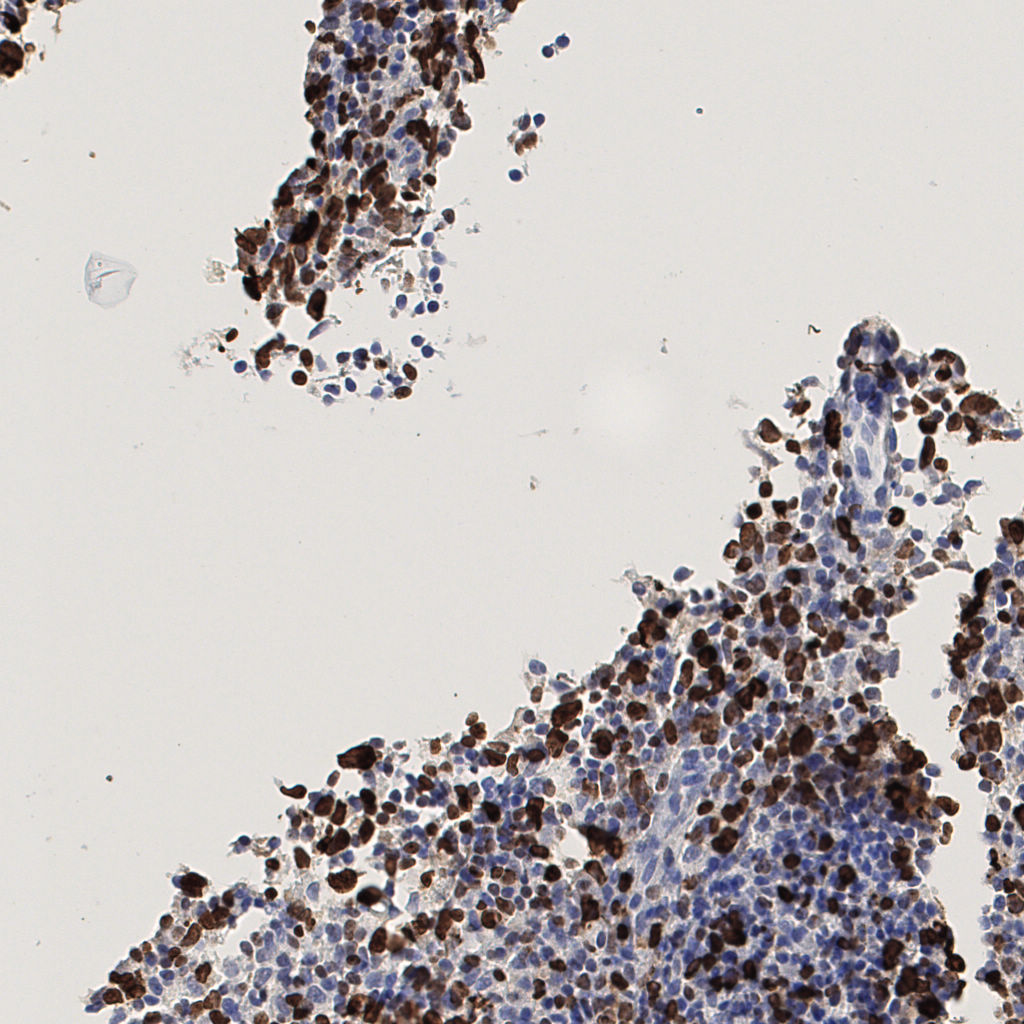

7.85%

Ki67 指数

阴 1104

阳 94

切片统计

总切片

1953

有效

288

已标记

有效率

15%

标记后

标记前